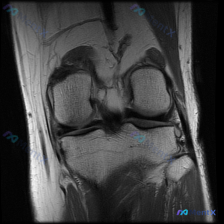

看到这张膝关节MRI的读片请求,目标是找半月板异常,但整理完全片发现这个病例的陷阱挺典型,分享出来给大家参考。

这是一张膝关节冠状位T1加权磁共振图像,只有单一层面单序列,我们先按结构捋一遍所见:

- 骨骼结构:股骨远端、胫骨近端骨皮质连续,没有明显骨折线;但整个骨髓腔在T1序列上是弥漫性中低信号,正常黄骨髓的高信号看不到了,关节面形态基本完整,没有明显骨质缺损塌陷

- 半月板:内外侧半月板都是均匀低信号,形态锐利,没有看到线状高信号穿透关节面,结构连续

- 韧带:内侧、外侧副韧带走行正常,纤维连续,没有明显中断或增粗

- 关节软组织:只有少量关节间隙信号,没有大量关节积液征象

- 关键异常灶:外侧胫骨平台关节面下方软骨下骨,可见边界相对清楚的局灶低信号区,和内侧对比信号不均匀,呈斑片状改变